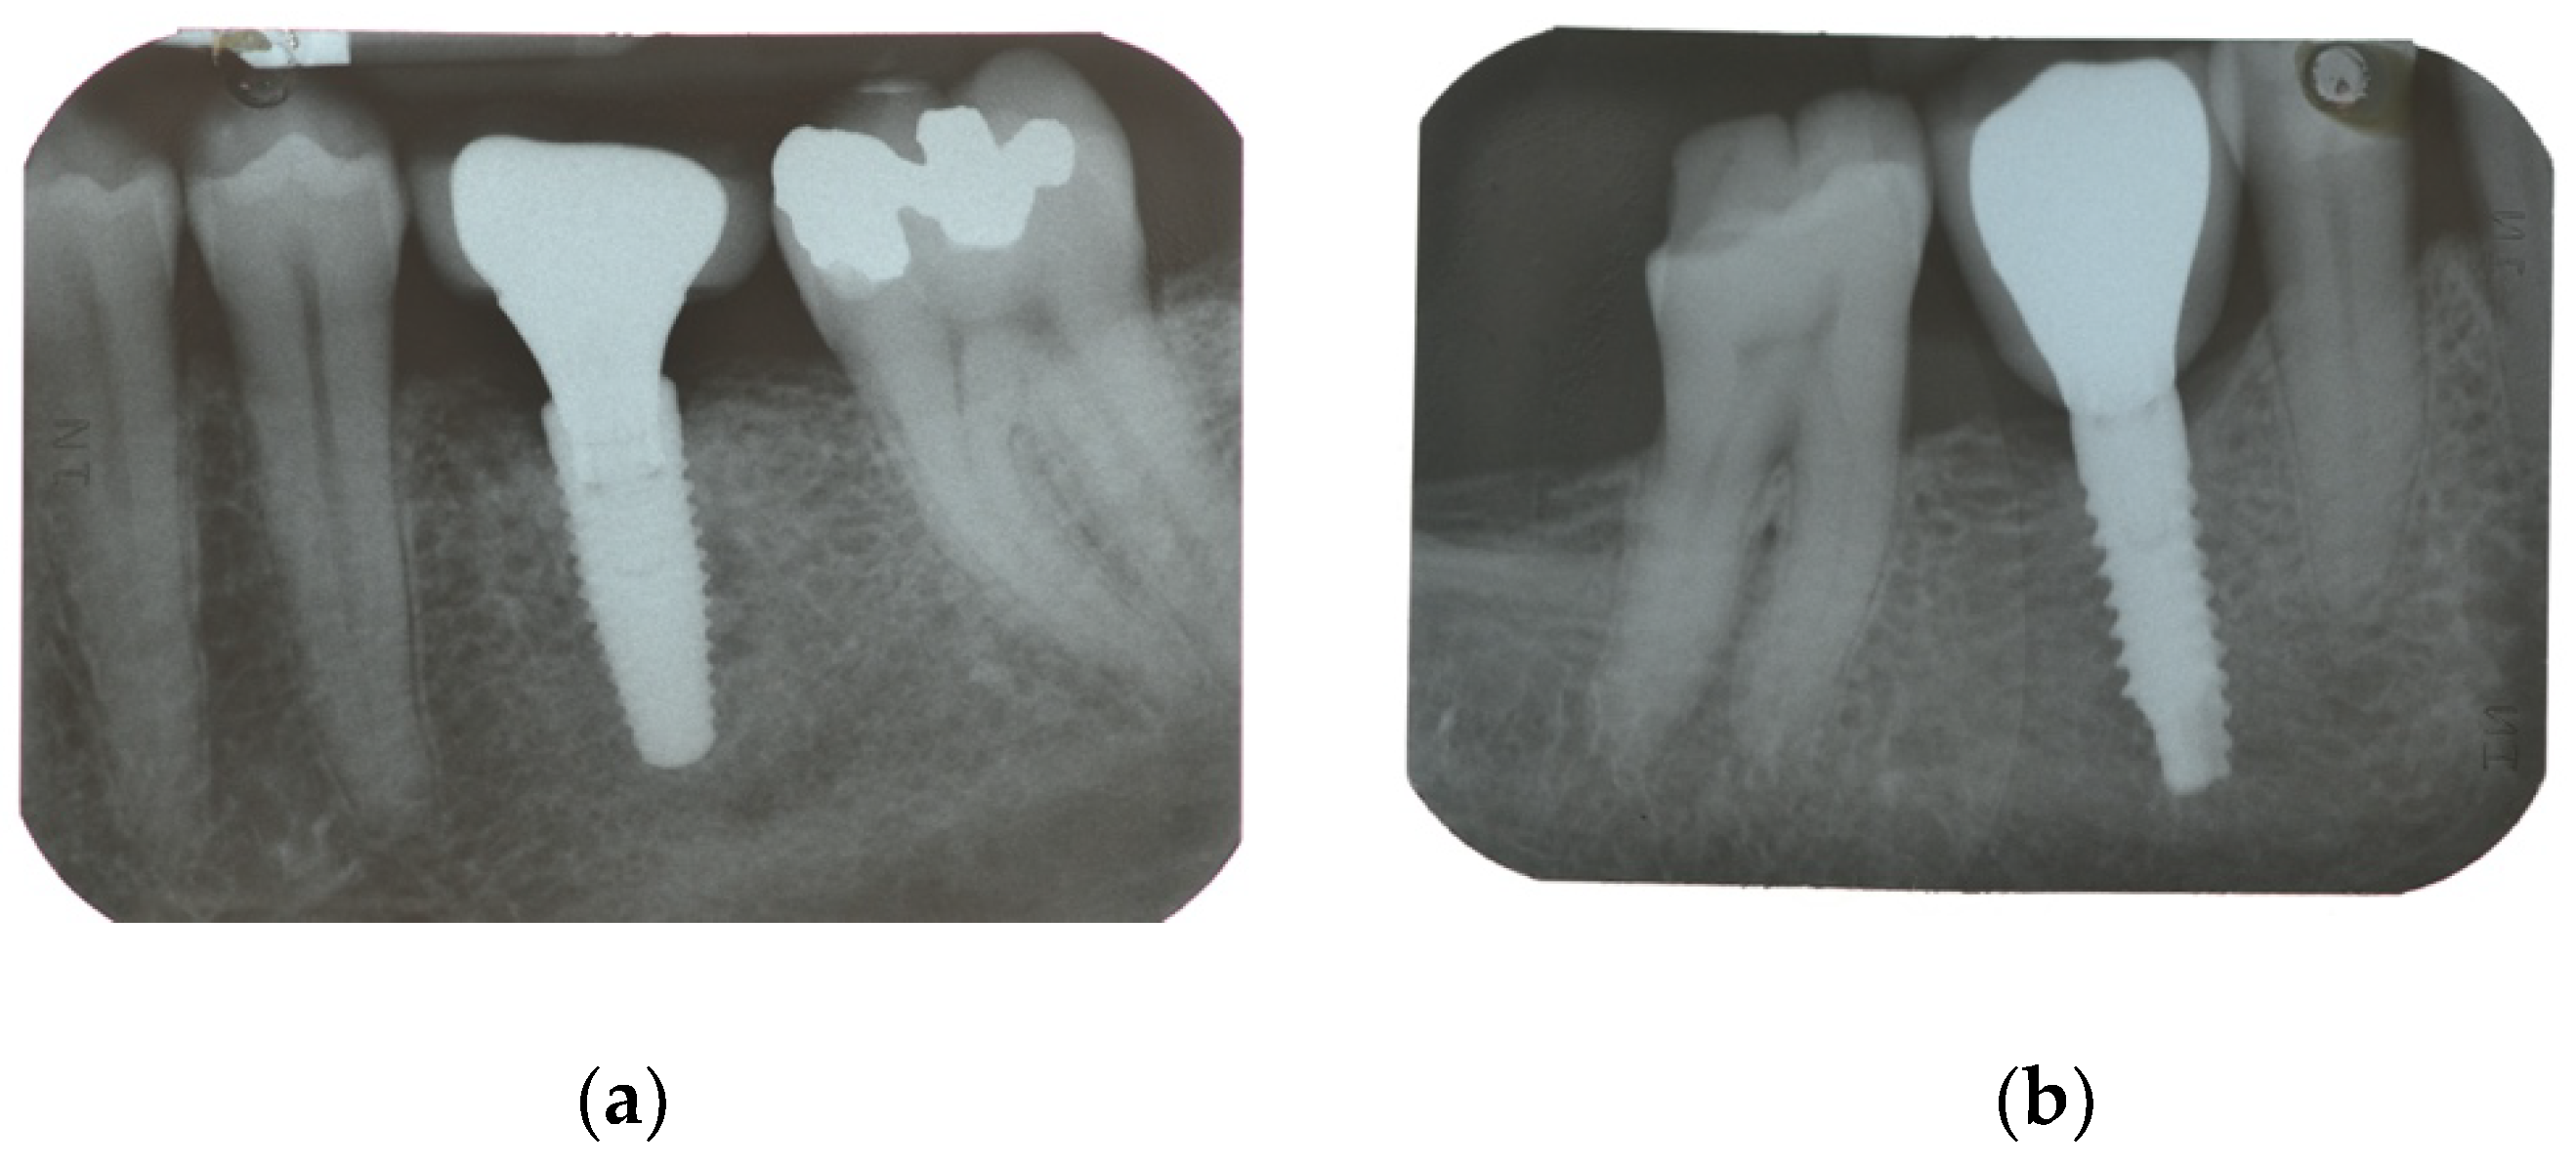

| Secondary Outcome | Marginal bone loss (MBL) | Marginal bone level changes were assessed using intraoral digital periapical radiographs at implant placement (baseline), and at after one year on function. Intraoral radiographs were taken with the parallel technique with customized holder. All the radiographs were evaluated under routine conditions. The software has been calibrated for every single image using the known distance of the implant diameter or length. The distance from the reference point at the implant neck to the first bone to implant contact were taken as the horizontal marginal bone level at both mesial and distal aspects. The average radiographic values of mesial and distal measurements were taken for each implant. Variation of the marginal bone levels at different time was taken as marginal bone loss. |

| Implant placement | 0.04 ± 0.06 (0.00 to 0.07); n = 15 | 0.01 ± 0.02 (0.00 to 0.02); n = 15 | 0.128 |

| One-year follow-up | 0.99 ± 0.71 (0.61 to 1.36); n = 14 | 0.65 ± 0.48 (0.40 to 0.91); n = 13 | 0.166 |

| Difference | 0.96 ± 0.72 (0.58 to 1.34) | 0.65 ± 0.48 (0.40 to 0.90) | 0.192 |